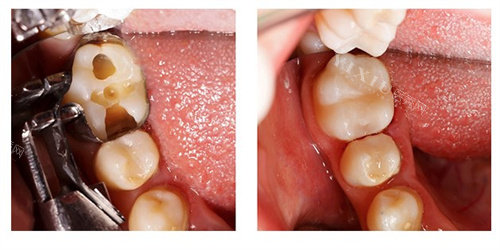

3M树脂补牙:300-700元起,修复蛀牙或龋齿,颜色与天然牙接近,部分活动期间单颗补牙可低至90元。

擅长领域:牙体牙髓病治疗、牙齿修复、牙列缺损修复等。

“阳医生补牙技术非常好,材料颜色和天然牙几乎一样,价格也实惠。”